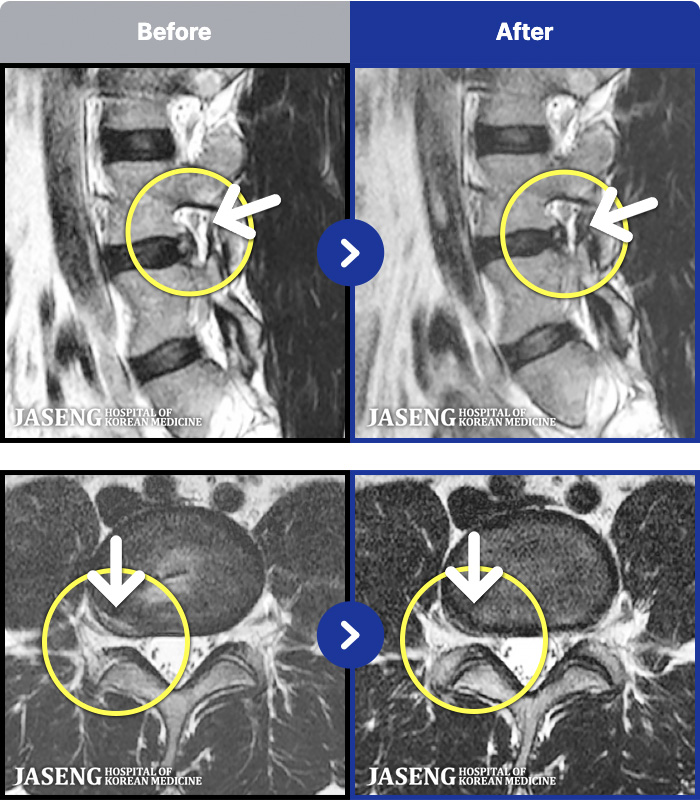

[뱸] 19.11.28~25.05.06

ȯںп Ǹ ǿ ԿǾ, ο ġ ۿ Ƿ ġḦ Ͻñ ٶϴ.